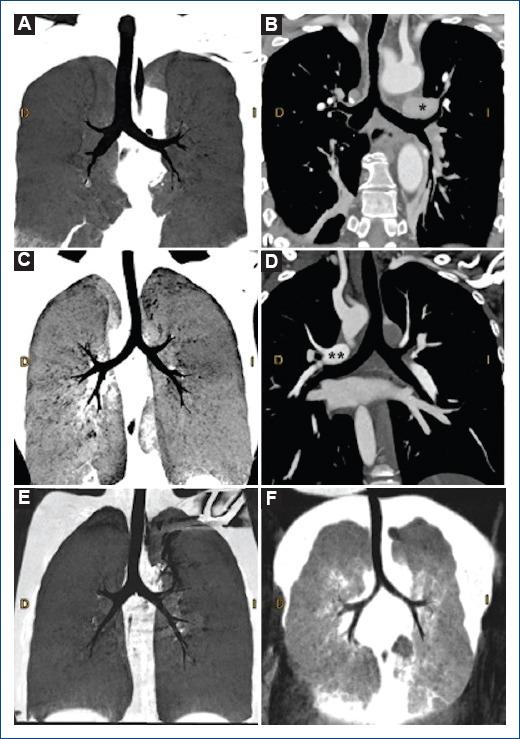

[心脏同构:一种多学科视角]

[Isomorfismo cardiaco: Una perspectiva multidisciplinaria].

Atrial isomerism describes complex anatomical findings with defects in the determination of lateralization; being a rare situation, with a prevalence of 1 in every 10.000 to 20.000 live births, with an incidence of up to 4% of all cardiac malformations. The diagnosis can be made in the neonatal age; however, clinical presentation is nonspecific. Depending on the spectrum of malformations, complex and invasive diagnostic tools may be required. Treatment is varied and can range from palliative surgery in view of univentricular physiology to total correction surgery for biventricular repair.

摘要

心房异构描述了在确定左右侧化方面存在缺陷的复杂解剖学发现;这是一种罕见情况,在每10000至20000例活产中发生率为1,占所有心脏畸形的比例高达4%。该诊断可在新生儿期做出;然而,临床表现并无特异性。根据畸形的范围,可能需要复杂且侵入性的诊断工具。治疗方法多样,从针对单心室生理状况的姑息性手术到双心室修复的完全矫正手术不等。